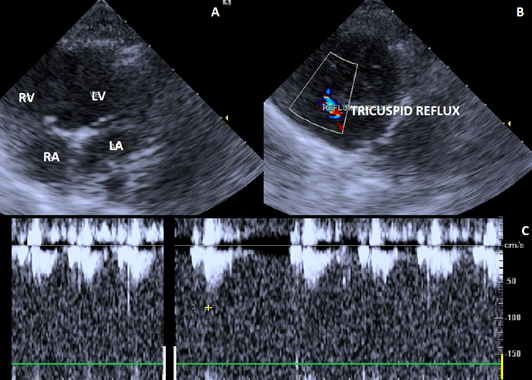

The echodoplercardiogram showed changes in the tricuspid (Figure 2), mitral (Figure 3) and pulmonary (Figure 4) valves. Due to the presence of pulmonary artery pressure greater than 25-30mmHg (35 mmHg), a diagnosis of pulmonary hypertension was definided.

Figure 2 Echocardiographic image showing right parasternal short-axis view of tricuspid valve. A. Tricuspid valve with degenerated appearance of the leaflets. B. Doppler study and color flow mapping showing moderate valve insufficiency. C. Spectral doppler tracing of tricuspid valve regurgitation.

The female dog in the case report during doppler echocardiography showed alterations in the tricuspid, mitral and pulmonary valves, with the presence of systolic pressure of 35mmHg, defining the condition of pulmonary hypertension. The doppler echocardiography is the choice method of diagnosis pulmonary hypertension, as it allows non-invasive measurement of blood pressure.7,8 The pulmonary artery pressure in healthy animals is approximately 20-25 mmHg during systolic and 6-10 mmHg in diastole. Pulmonary hypertension is identified by systolic pressure greater than 25-30 mmHg and mean pressure around 20 mmHg.1,2 The right heart catheterization is the standard test in humans to diagnose pulmonary hypertension.9 However, in veterinary medicine, this method is not widely used, due to the need sedation of the patient, which can worsen the clinical condition of the animal.